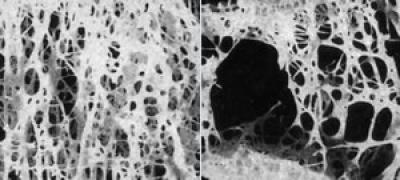

COLUMBIA, Mo. – Osteoporosis affects more than 200 million people worldwide and is a serious public health concern, according to the National Osteoporosis Foundation. Resistance training often is recommended to increase and prevent loss of bone mineral density (BMD), although previous studies that examined the effects of resistance training in men produced varied results. Now, in a new study, University of Missouri researchers have found that high-impact activities, such as running, might have a greater positive effect on BMD than resistance training.

In the study, the researchers determined the effects of long-term running, cycling, and resistance training on whole-body and regional BMD, taking into account the effects of body weight and composition, in men ages 19 to 45. After adjusting for differences in lean body mass, the researchers found that runners had greater spine BMD than cyclists. Lean body mass was positively associated with BMD in both resistance-trained individuals and cyclists but not in runners; therefore, high-impact activity may override the benefits of lean body mass on BMD, Hinton said.